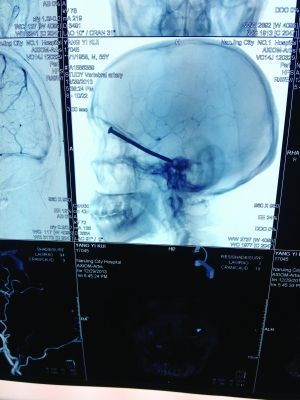

CT投影

CT投影結(jié)果,把大家嚇了一跳:楊先生腦子里居然有一根長釘,從眼眶一直“伸”到了接近后腦勺的位置!鐵釘細(xì)長略帶彎曲,長達(dá)8厘米。根據(jù)推測,鐵釘應(yīng)該是從上眼眶的縫隙中飛入,一直插進(jìn)腦顱中,末端還有一個(gè)小小凸出的釘帽。